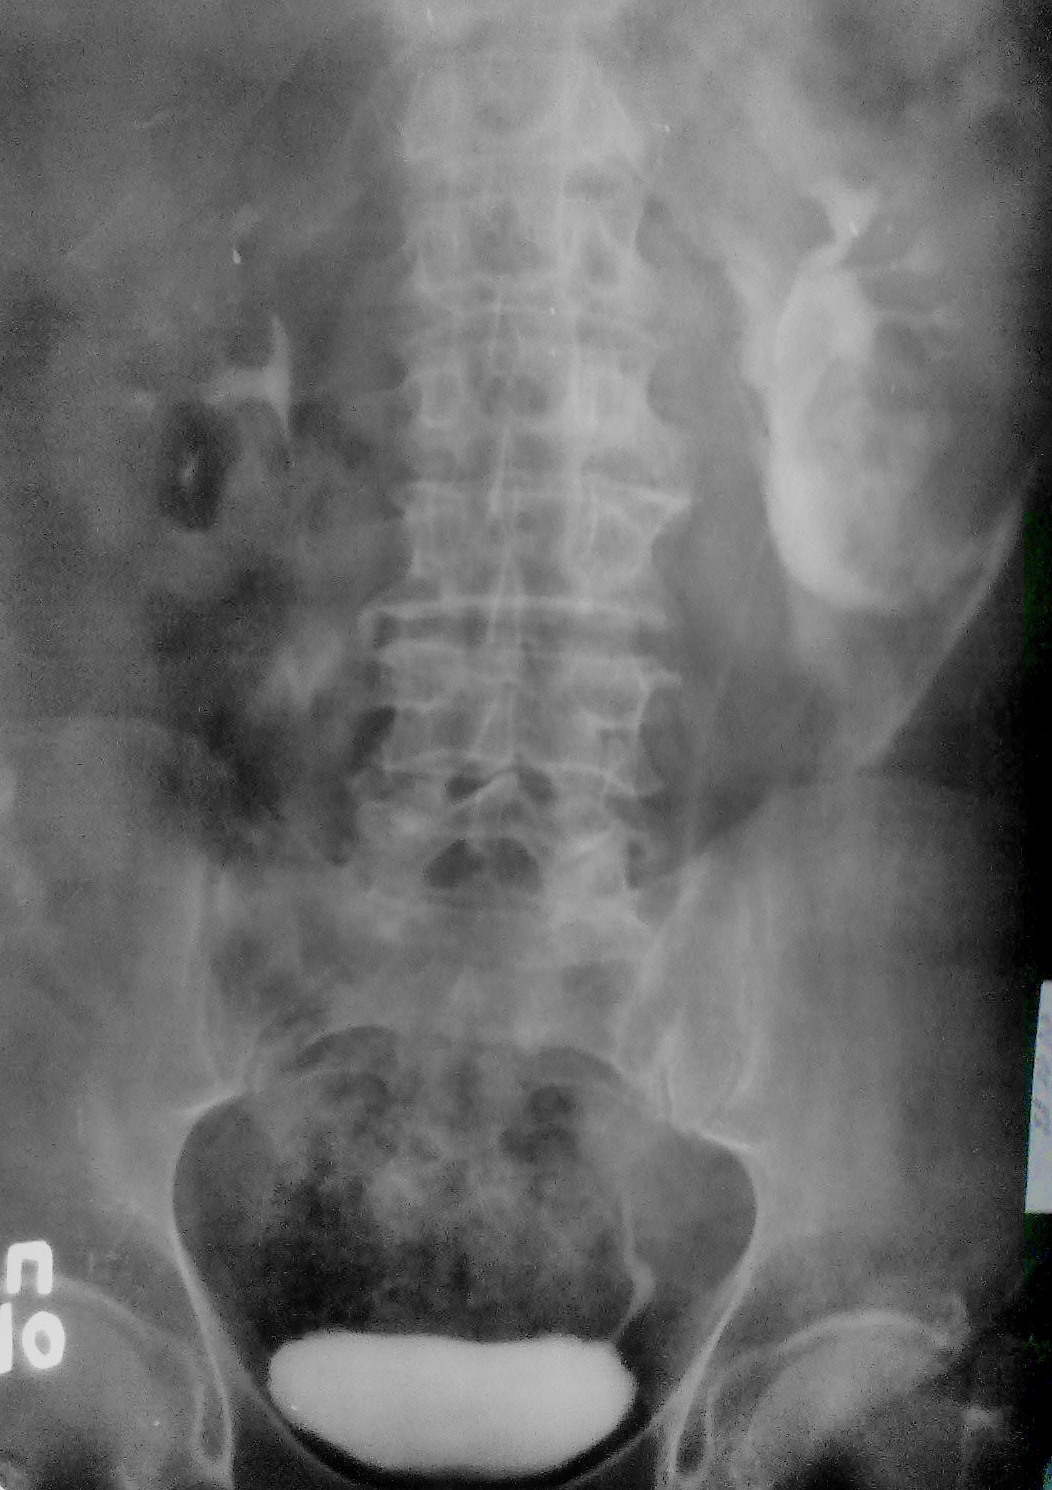

В\в урография

Представляю Вам в\в урографию без коментариев. Случай классический.

Разрыв почки? Затек контраста?

Все правильно, это тоже криминальная травма, сукапсулярный и капсулярный разрыв нижнего полюса левой почки и затек контраста паранефрально...

Спасибо за "рихтовку" снимков, просто хотелось показать как выглядит затек в паренхиму, под капсулу и вне капсулы...в этом плане случай очень показателен. Кстати, больного не оперировали, заживление, он жив и, как видите, судится с обидчиками....